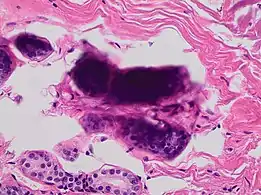

'Formalin pigment artifacts

'Formalin pigment artifacts Air bubble entrapment artifact in a shoulder joint biopsy